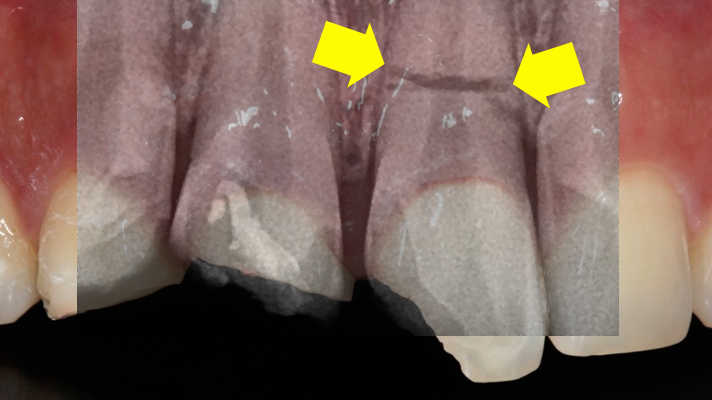

Clinical case: Extraction, immediate placement & loading using

R2GATE solution in aesthetic zone

- Courtesy of Dr. Jong-Cheol Kim, Korea-